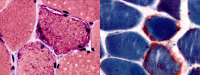

A 48-year-old man was admitted for workup of stroke-like symptoms and generalised tonic-clonic seizures. History and examination revealed that the patient had background diagnoses of type 2 diabetes mellitus, epilepsy and had suffered a temporal lobe infarct 3 years ago. The unusual presentation and physical findings, along with subsequent MRI findings led to a diagnosis of mitochondrial myopathy, encephalopathy, lactic acidosis and stroke-like episodes (MELAS). MELAS is a mitochondrial disorder typified by the aforementioned symptoms, and is typically diagnosed in the first two decades of life.